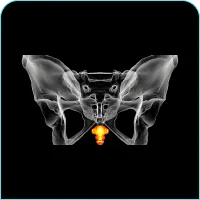

The spine is a complex of vertebrae, discs, joints, and ligaments that are connected with numerous nerves and muscle tendons. It gives stability, mobility, and safety to the spinal cord. Injury, degeneration, stress, and misalignment of any of these parts result in a situation where someone experiences constant pain and has limited movements.